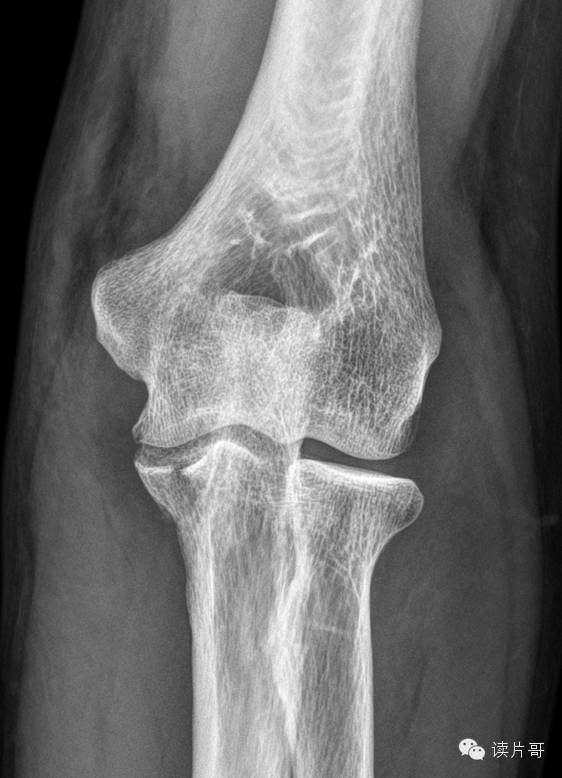

肘关节尺骨骨折 读片哥 微信公众号文章阅读 Wemp

尺骨鹰嘴的症状和体征 尺骨鹰嘴骨折 尺骨 骨折不愈合

尺骨鹰嘴骨折 医联